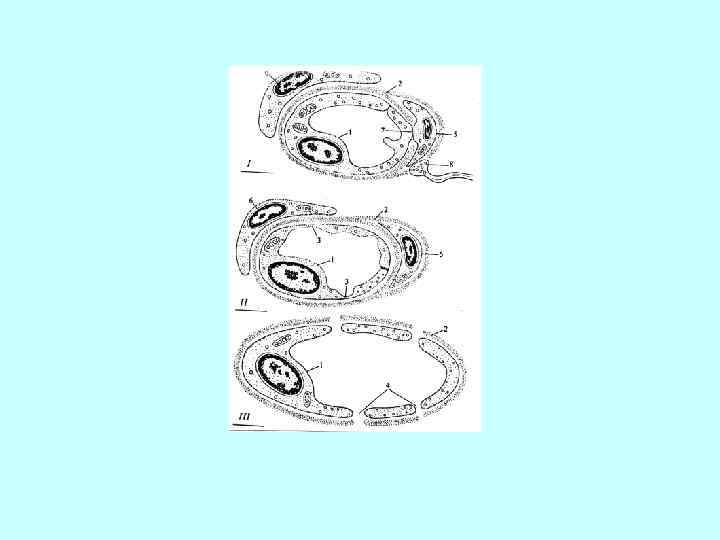

Капилляры, артериолы, венулы – сосуды мягкой мозговой оболочки. Окр. гем. -эозин. Тотальный препарат Капилляры, артериолы, венулы – сосуды мягкой мозговой оболочки. Окр. гем. -эозин. Тотальный препарат